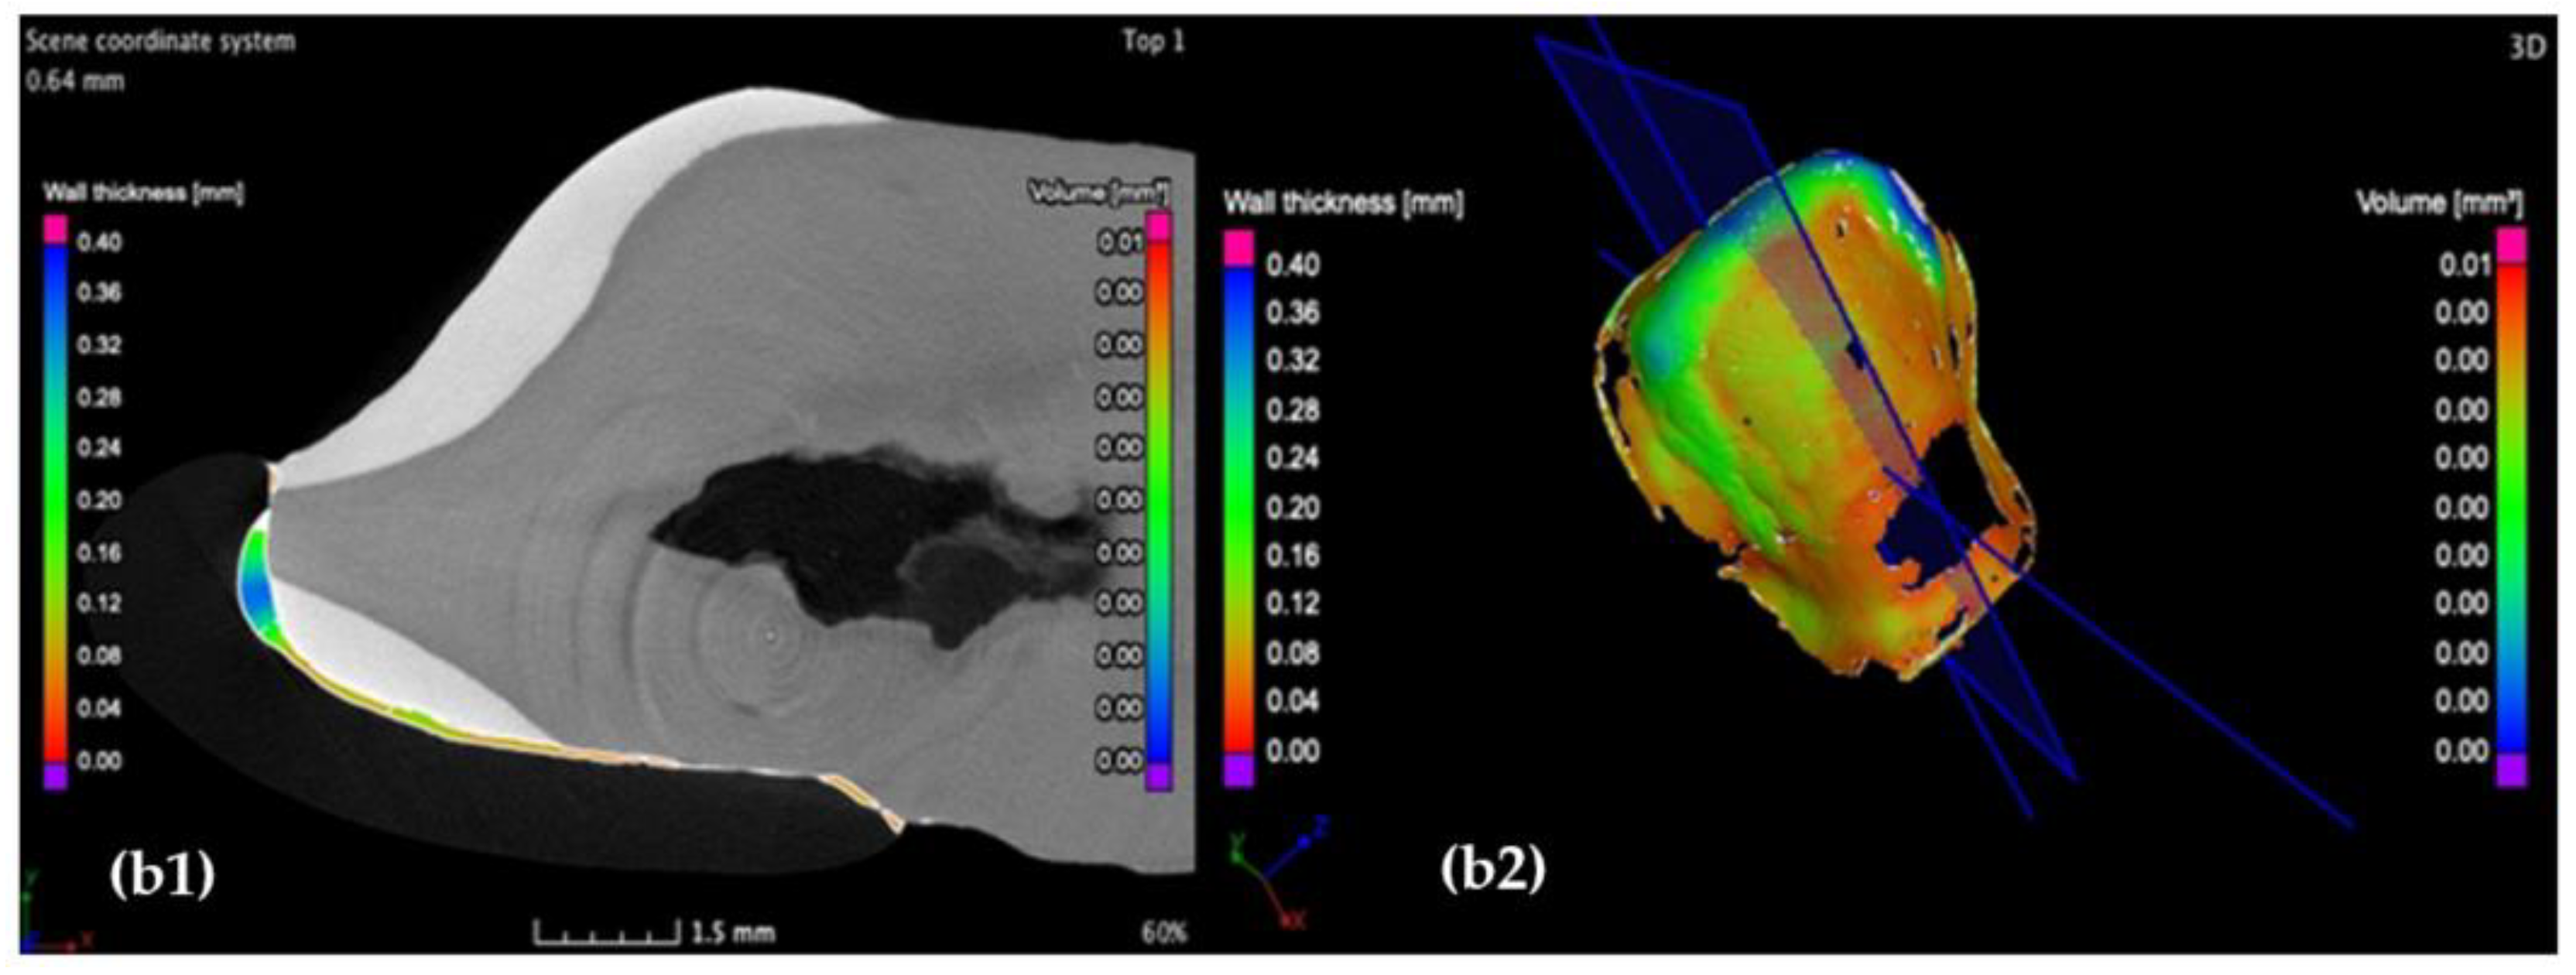

3.2. Micro-CT

3.3. Mathematical Modeling of the Micro-CT Results